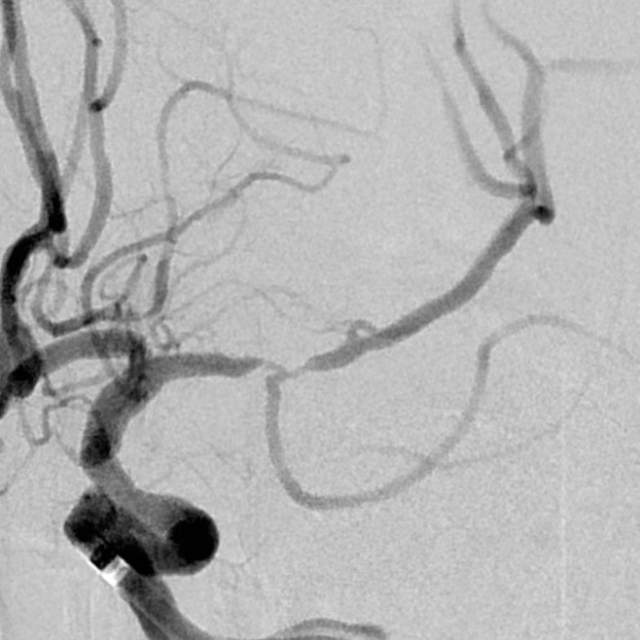

​2、第二个患者:我们给予一期外科干预后,一个月后检查发现,狭窄的部位和术后即刻相比是稳定的,二期安全的植入支架,血流完全恢复正常,顺利出院;

术前

术后即刻

术后一个月随访稳定,给予支架植入,血流恢复正常,分支血管保留良好